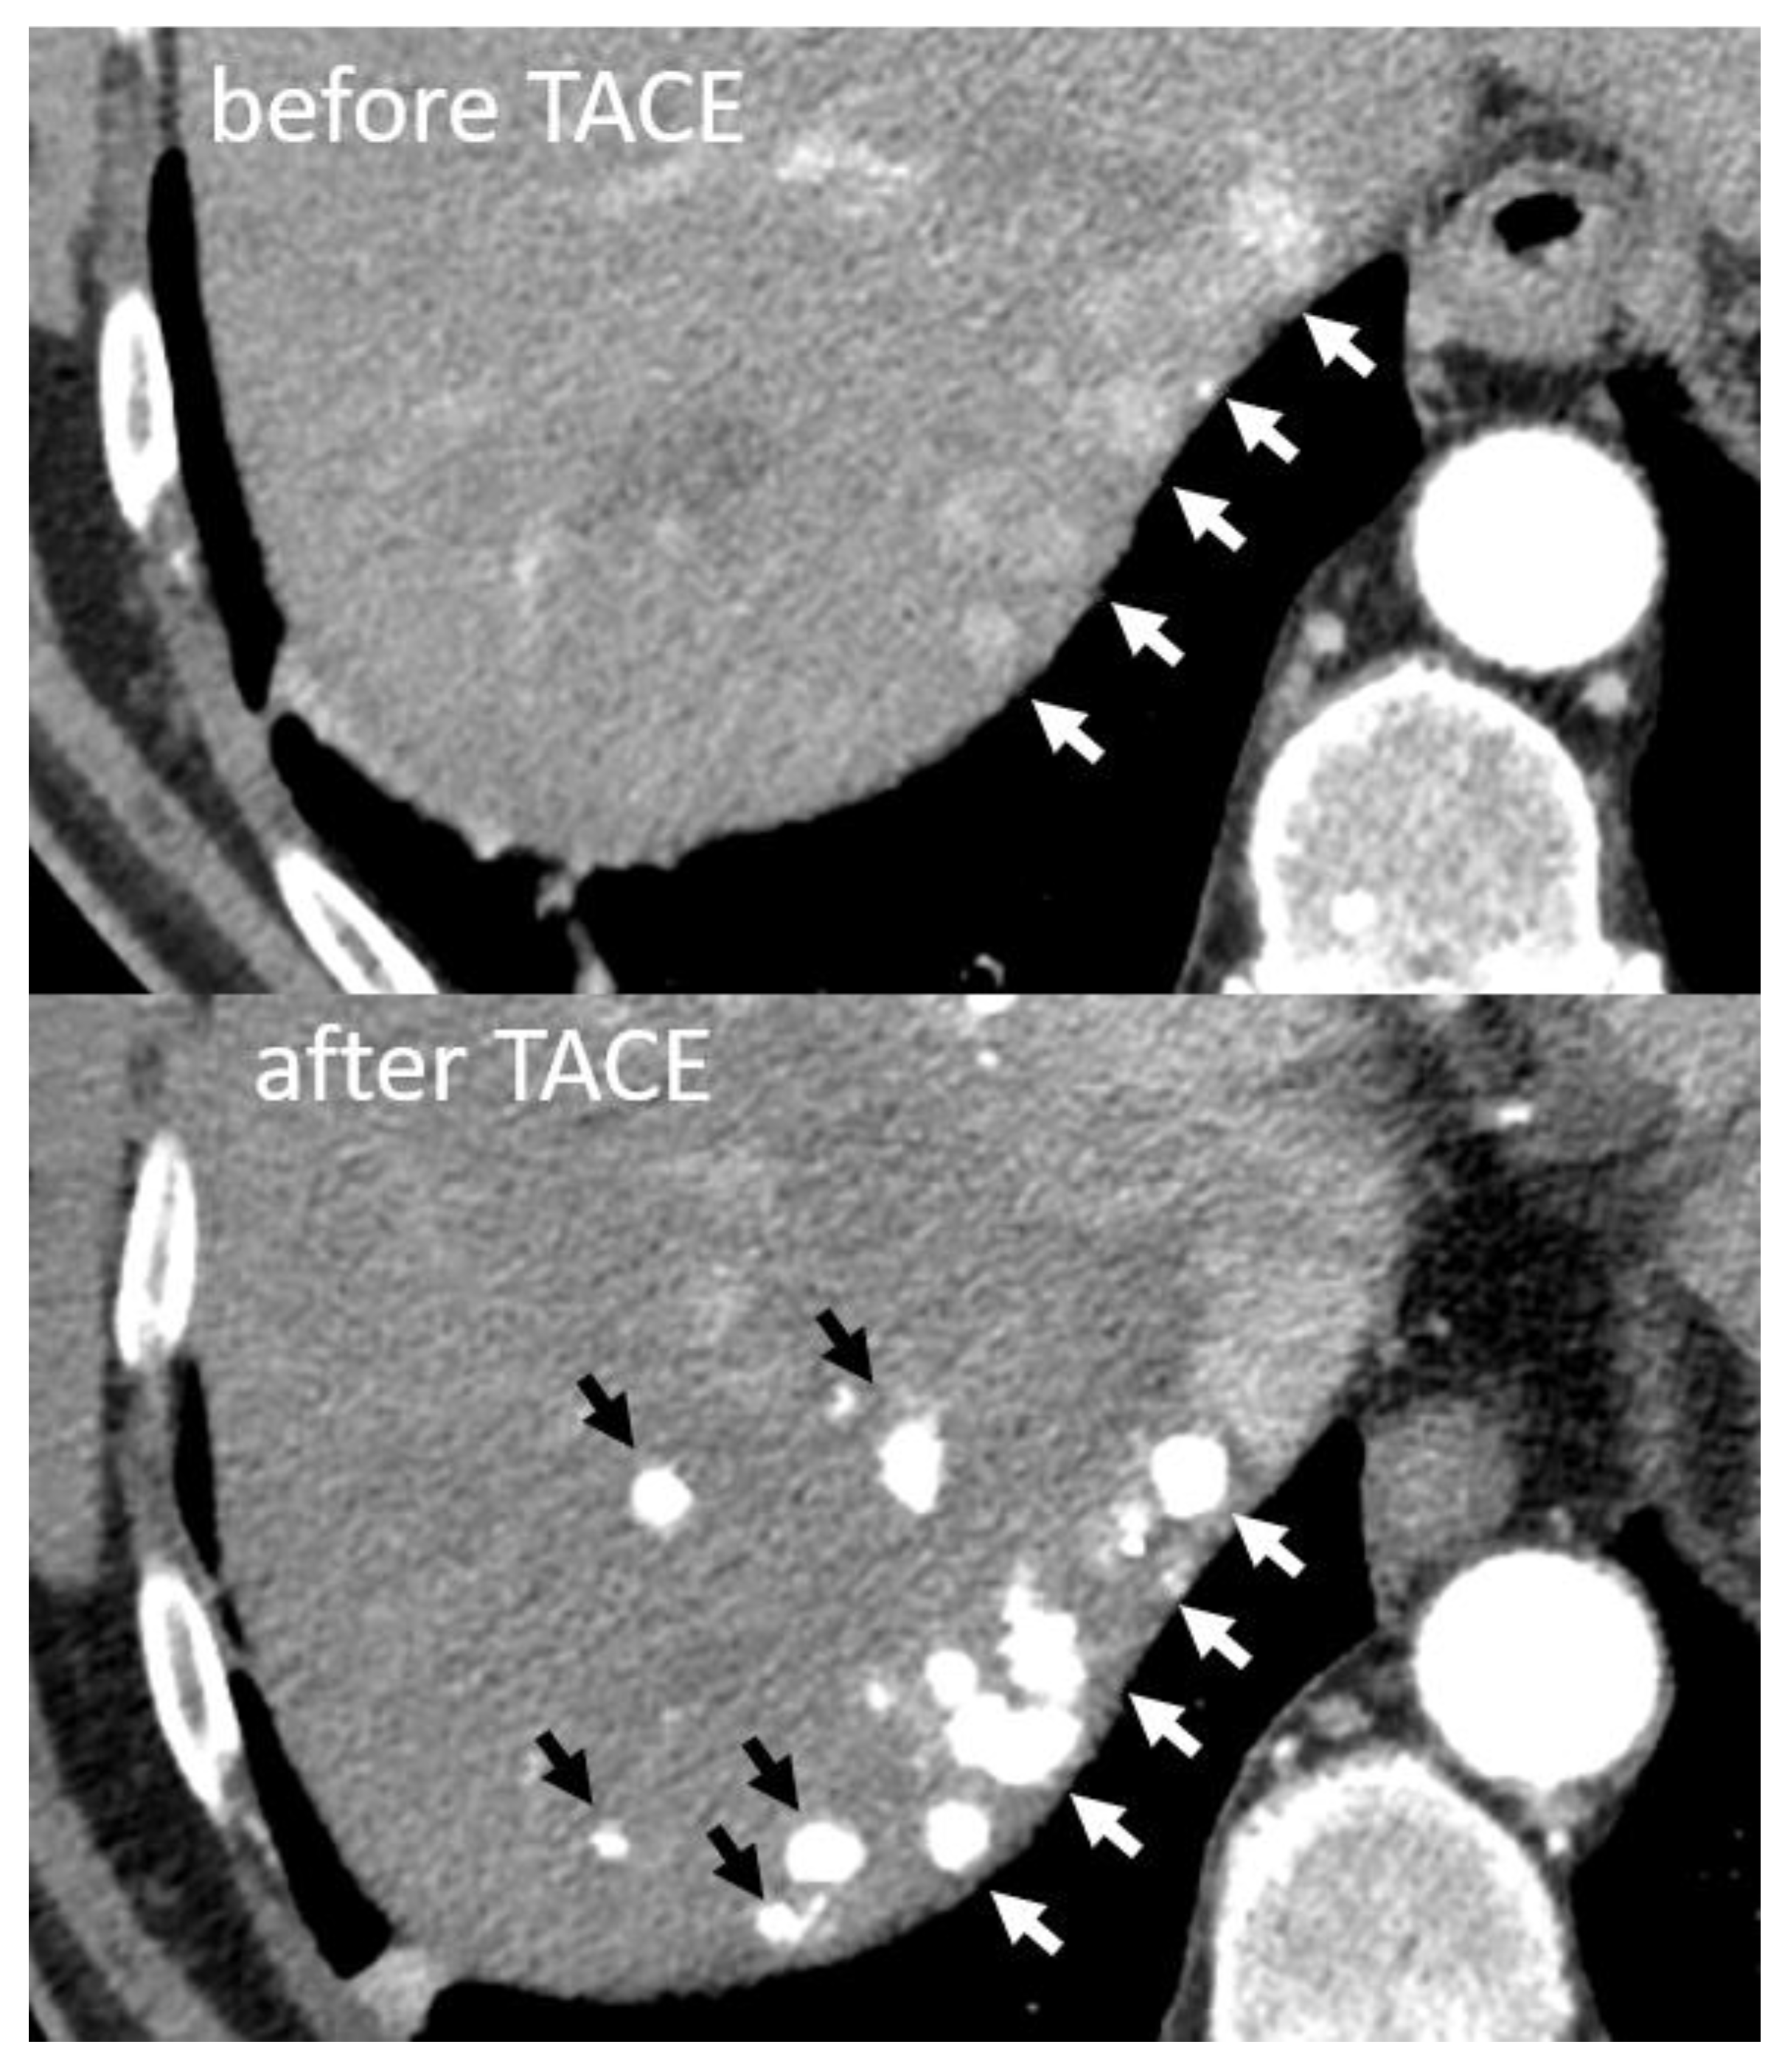

- Najmi Varzaneh, F.; Pandey, A.; Aliyari Ghasabeh, M.; Shao, N.; Khoshpouri, P.; Pandey, P.; Zarghampour, M.; Fouladi, D.; Liddell, R.; Anders, R.A.; et al. Prediction of post-TACE necrosis of hepatocellular carcinoma usingvolumetric enhancement on MRI and volumetric oil deposition on CT, with pathological correlation. Eur. Radiol. 2018, 28, 3032–3040. [Google Scholar] [CrossRef] [PubMed]

- Takayasu, K.; Arii, S.; Matsuo, N.; Yoshikawa, M.; Ryu, M.; Takasaki, K.; Sato, M.; Yamanaka, N.; Shimamura, Y.; Ohto, M. Comparison of CT findings with resected specimens after chemoembolization with iodized oil for hepatocellular carcinoma. Am. J. Roentgenol. 2000, 175, 699–704. [Google Scholar] [CrossRef]

- Miyayama, S.; Mitsui, T.; Zen, Y.; Sudo, Y.; Yamashiro, M.; Okuda, M.; Yoshie, Y.; Sanada, T.; Notsumata, K.; Tanaka, N.; et al. Histopathological findings after ultraselective transcatheter arterial chemoembolization for hepatocellular carcinoma. Hepatol. Res. 2009, 39, 374–381. [Google Scholar] [CrossRef]